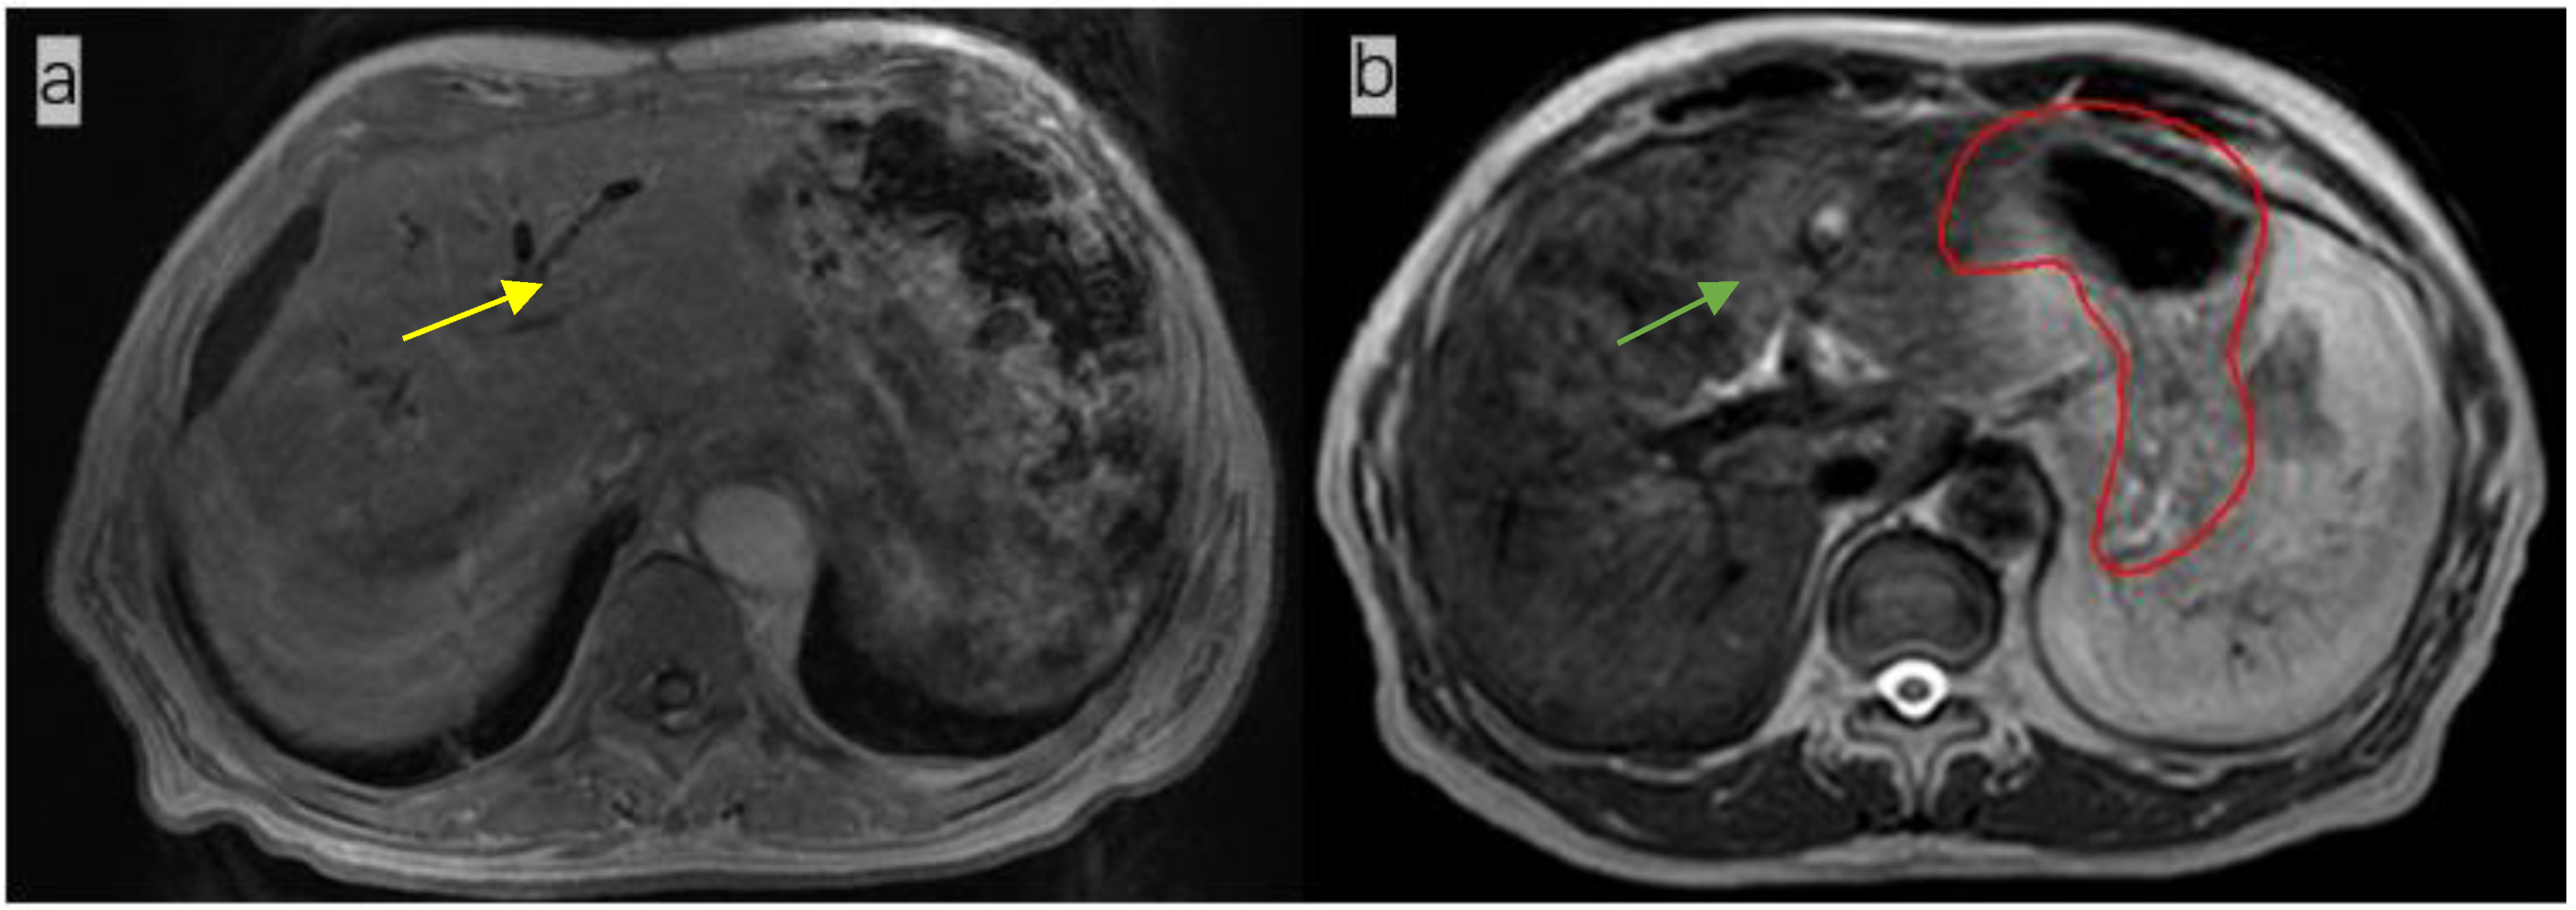

Figure 1.

(a). Magnetic resonance image (MRI) of a patient (not the patient treated in this study) not treated with anisodamine; notice that the outline of the stomach is blurred (yellow arrow); (b) MR image of the patient treated with anisodamine; notice that the outline of the stomach is clearer (green arrow; the red line indicates the contours of the whole stomach).